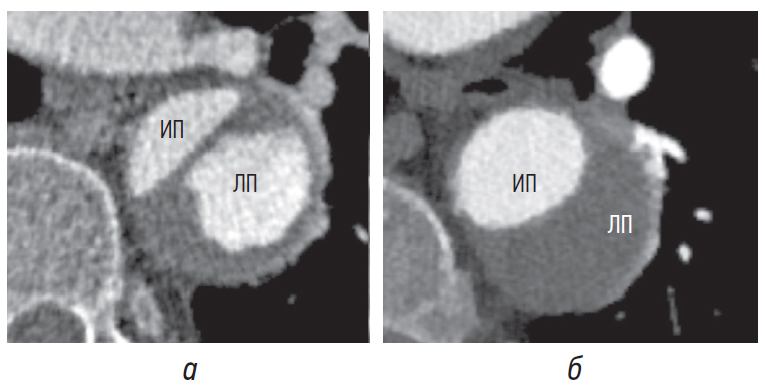

Характеристика интимомедиального лоскута

Характеристика интимомедиального лоскута дополнительно помогает не только в дифференцировке истинного просвета аорты от ложного, но и при определении острой и хронической диссекции. Это возможно благодаря изменениям интимомедиального лоскута при переходе от острой стадии к хронической [10].

Для острой диссекции более характерны заметная кривизна и волнистость подвижного лоскута (рис. 7, а), тогда как для хронической диссекции — плоский, фиксированный и утолщенный лоскут на большем его протяжении (рис. 7, б) [6–8].

Рис. 7. Интимомедиальный лоскут (стрелки) при острой (а) и хронической (б) диссекции. ИП — истинный просвет, ЛП — ложный просвет

Направление кривизны лоскута в сочетании с другими признаками помогает отличить истинный просвет от ложного, поскольку лоскут чаще всего изогнут в сторону ложного просвета (рис. 8, а) и реже — в сторону истинного (рис. 8, б) [8].

Рис. 8. Интимомедиальный лоскут кривизной (стрелки) обращен в сторону ложного просвета (а), в сторону истинного просвета (б). ИП — истинный просвет, ЛП — ложный просвет